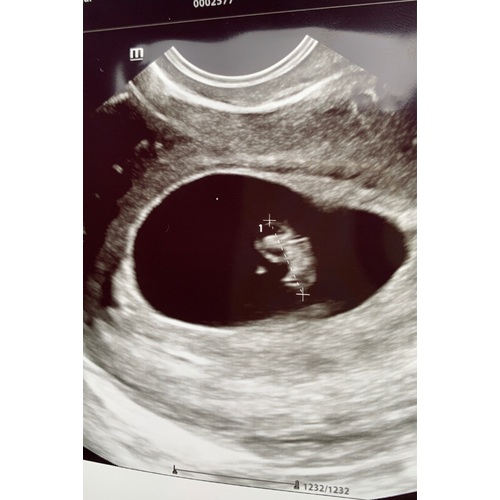

Dit was ons dochtertje met 7+2 weken zwangerschap. Ze was toen 11mm en haar hartje klopte al op een mooi tempo. Veel succes donderdag!

Pff dat is heel naar om mee te maken! Ik snap dat je het nu extra spannend vindt. Dit was onze echo met 7 weken. Links de dooierzak en rechts de baby.

7+2 weken